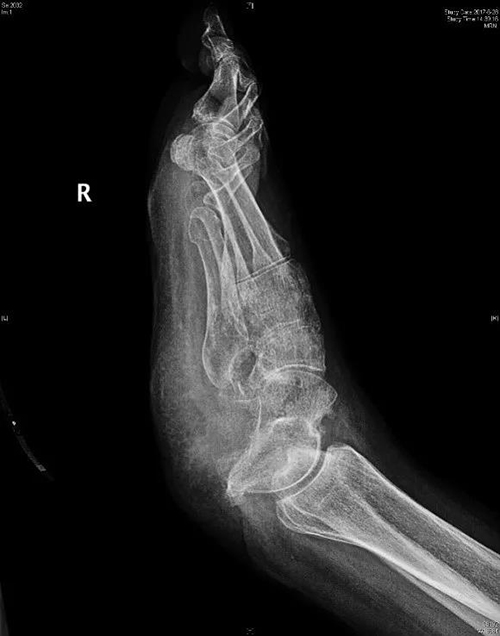

主诉:因右跟骨骨髓炎跟骨摘除术后3月余入院。

病史:患者于2015年9月1日在外院因右跟骨骨折行骨折切开复位内固定术,术后出现感染,刀口流脓,形成骨髓炎,多次手术清创治疗效果不佳。

诊疗经过:王主任接诊此患者时,患者整个跟骨完全感染坏死,创面感染脓性渗出非常严重,大量的坏死毒素吸收,患者持续高热。无奈之下,在2017年3月10日,王主任为其施行了右跟骨骨髓炎病灶清除术,右跟骨完全摘除,术后抗感染治疗,患者恢复良好,拄拐行走,骨髓炎未复发,3个月内未再出现感染征象。

术前X线片可见跟骨完全缺失